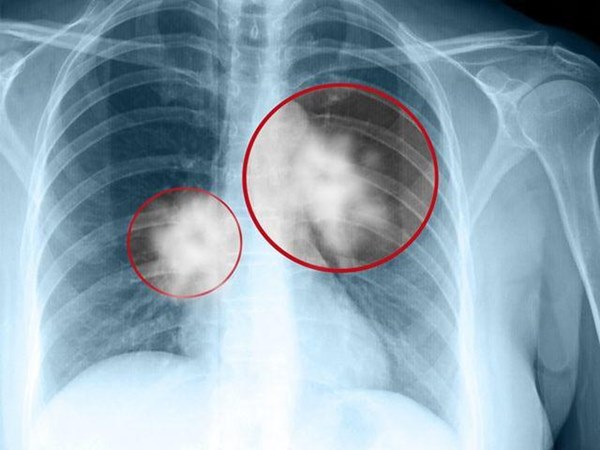

Hai năm trước, chồng bà Trần phát hiện bị ung thư phổi, sau một năm chữa trị, ông đã qua đời. Khi chồng bị ung thư phổi qua đời, bà mới cảm thấy bản thân mình thời gian dài thường xuyên khó thở. Vì nghi ngờ bản thân cũng có thể mắc bệnh giống chồng, bà Trần mới đến bệnh viện để kiểm tra. Sau khi thực hiện CT Scan ngực liều thấp (LDCT), quả nhiên phát hiện khối u 0,3cm.

Phát hiện sớm và điều trị sớm có tác dụng đáng kể trong việc chữa ung thư phổi. Bác sĩ Lại Cơm Minh cho rằng, ung thư phổi được phẫu thuật cắt bỏ trong vòng một centimet và tỷ lệ chữa khỏi là 95%. Do đó, kiểm tra thể chất thường xuyên là rất quan trọng, đặc biệt đối với các nhóm có nguy cơ mắc ung thư phổi cao. Hiện tại, LDCT có thể phát hiện tổn thương phổi dưới 0,3 cm.